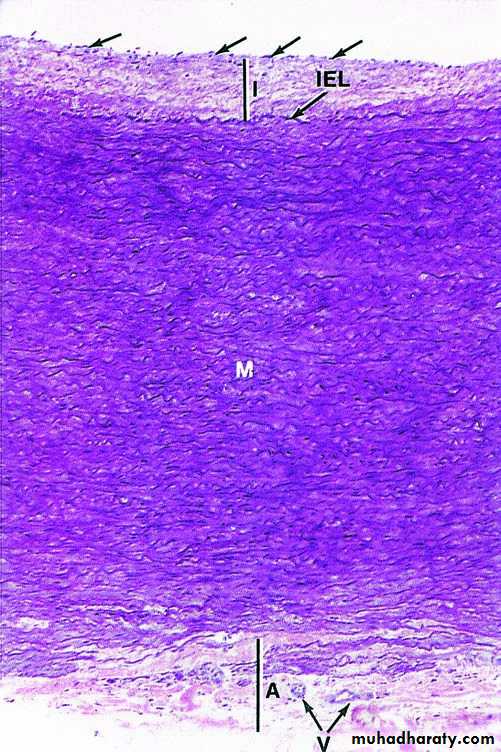

Large veins have a muscular tunica media (TM) that is very thin compared to the tunica adventitia (TA) composed of dense irregular connective tissue. The wall is often folded as shown here. The tunica intima here projects into the lumen as a valve (V), composed of the subendothelial connective tissue with endothelium on both sides. X100, PT.Comparison of the three major layers or tunics in the largest artery and vein. (a) Aorta, (b) vena cava. Simple squamous endothelial cells (arrows) line the intima (I) that has subendothelial loose connective tissue and is separated from the media by the internal elastic lamina (IEL), A sheet of elastin. The Media (M) contains many elastic lamellae and elastic fibers (EF) Alternating with layers of smooth muscle. The media is much thicker in large arteries than veins, with relatively more elastin. Elastic fibers are also present in the outer tunica adventitia (A), which is relatively thicker in large veins. Vasa vasorum (V) are seen in the adventitia of the aorta. The connective tissue of the adventitia always merges with the less dense connective tissue around it. Both X122. elastic stain.